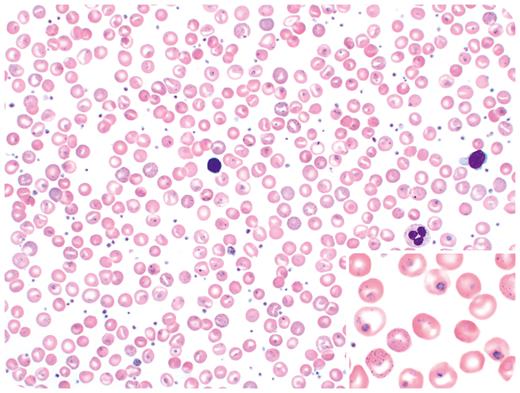

A 58-year-old woman presented for a routine annual exam. A complete blood count showed moderate macrocytic anemia (hemoglobin, 9.0 g/dL; mean corpuscular volume, 127 fL) and thrombocytosis (633 000/μL). Her vitamin B12 and folate levels were normal. Peripheral smear showed increased polychromasia, basophilic stippling, Howell-Jolly bodies, and Pappenheimer bodies (Wright-Giemsa stain, 50× objective, total magnification ×500). Additionally, some red blood cells (RBCs) showed pleomorphic ring-like forms with purple dots, resembling a parasitic infection by Babesia or Plasmodium spp (inset, 100× objective, total magnification ×1000). Thorough exploration into the patient’s past medical history revealed that she was diagnosed with hemoglobin Southampton at 1 year of age and had a splenectomy at age 4 years.

Hemoglobin Southampton (Casper) is a rare, unstable hemoglobinopathy caused by a point mutation in the HBB gene (c. 320T>C, p.L107P) resulting in distortion of the tertiary structure of the hemoglobin molecule, leading to membrane damage and RBC destruction. Hepatosplenomegaly, chronic hemolytic anemia, and methemoglobinemia are common features. Macrocytosis is sometimes observed, and evaluation for vitamin B12 and folate deficiency is recommended due to chronic hemolysis and the constant regenerative nature of the bone marrow. Splenectomy helps decrease the transfusion requirement and chronic hemolysis. This case highlights the importance of obtaining patient history and clinical symptoms when reviewing blood smears, as RBC inclusions in these rare unstable hemoglobinopathies can be mistaken for parasitic infections.